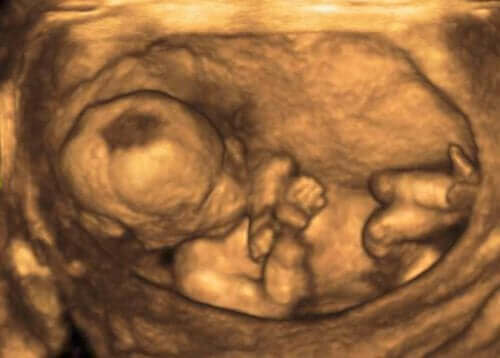

Lapsivesi ympäröi kohdussa kasvavaa sikiötä koko raskauden ajan, ja sillä on merkittävä rooli sikiön kehityksen kannalta. Mitä lapsivesi oikeastaan on ja miksi se on niin tärkeää raskauden kannalta? Tässä artikkelissa vastaamme näihin kysymyksiin ja kerromme myös muita mielenkiintoisia faktoja lapsivedestä.

Lapsivesi on sikiötä suojaavien vesi- ja suonikalvon sisällä olevaa nestettä, jonka ympäröimänä sikiö kelluu raskauden ajan. Lapsiveden koostumus ja määrä muuttuvat raskauden edetessä. Sen määrä lisääntyy aina 32. raskausviikolle asti, minkä jälkeen määrä pysyy hetken samana ennen kuin se alkaa vähentyä 40. raskausviikon jälkeen. Normaali lapsivesi on väriltään kirkasta, vaaleaa tai vaaleanpunertavaa ja tuoksultaan makeahkoa. Vihreä tai ruskea lapsivesi on poikkeavaa ja tarkoittaa sikiön ulostaneen veteen.

Alku- ja keskiraskauden aikana lapsivesi koostuu istukan, napanuoran ja vesikalvon soluista. Kun sikiölle raskauden viimeisellä kolmanneksella kehittyy virtsaamis- ja nielemiskyky, lapsivesi koostuu pääasiassa sikiön virtsasta ja suun ja nenän eritteistä sekä sen keuhkoista peräisin olevasta nesteestä.